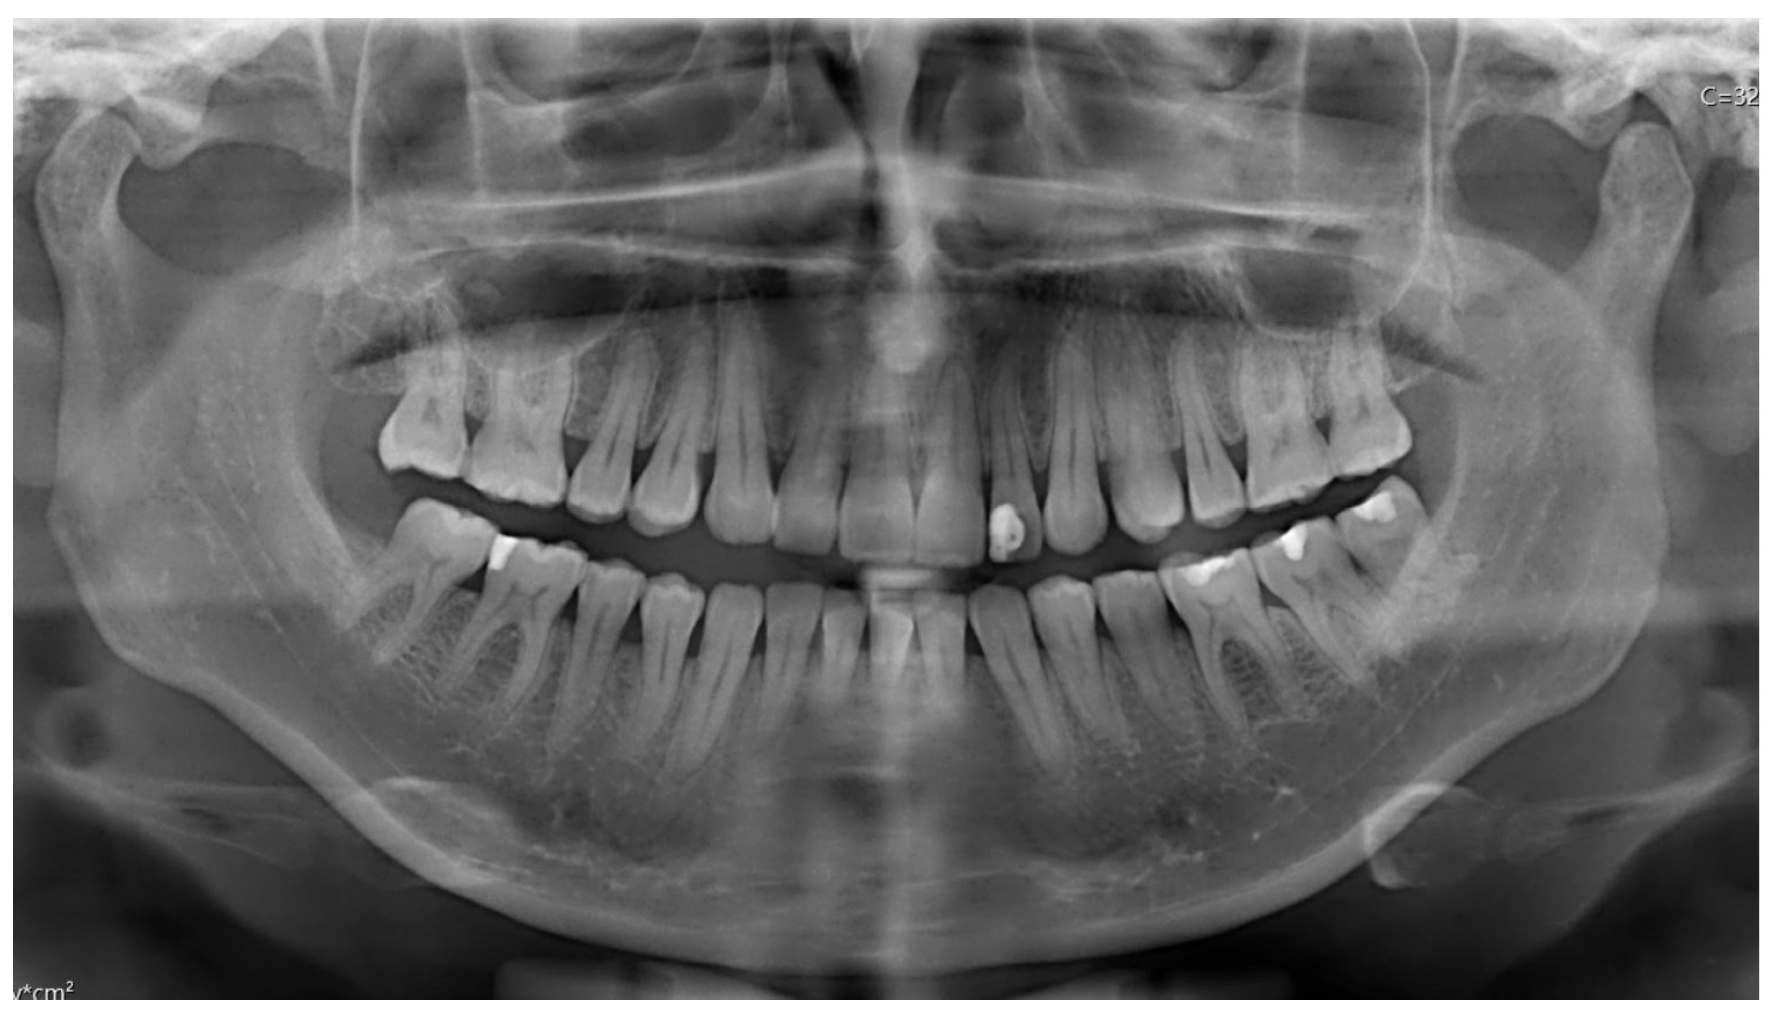

- Case 1

- Case 2

- Case 4

- Case 5